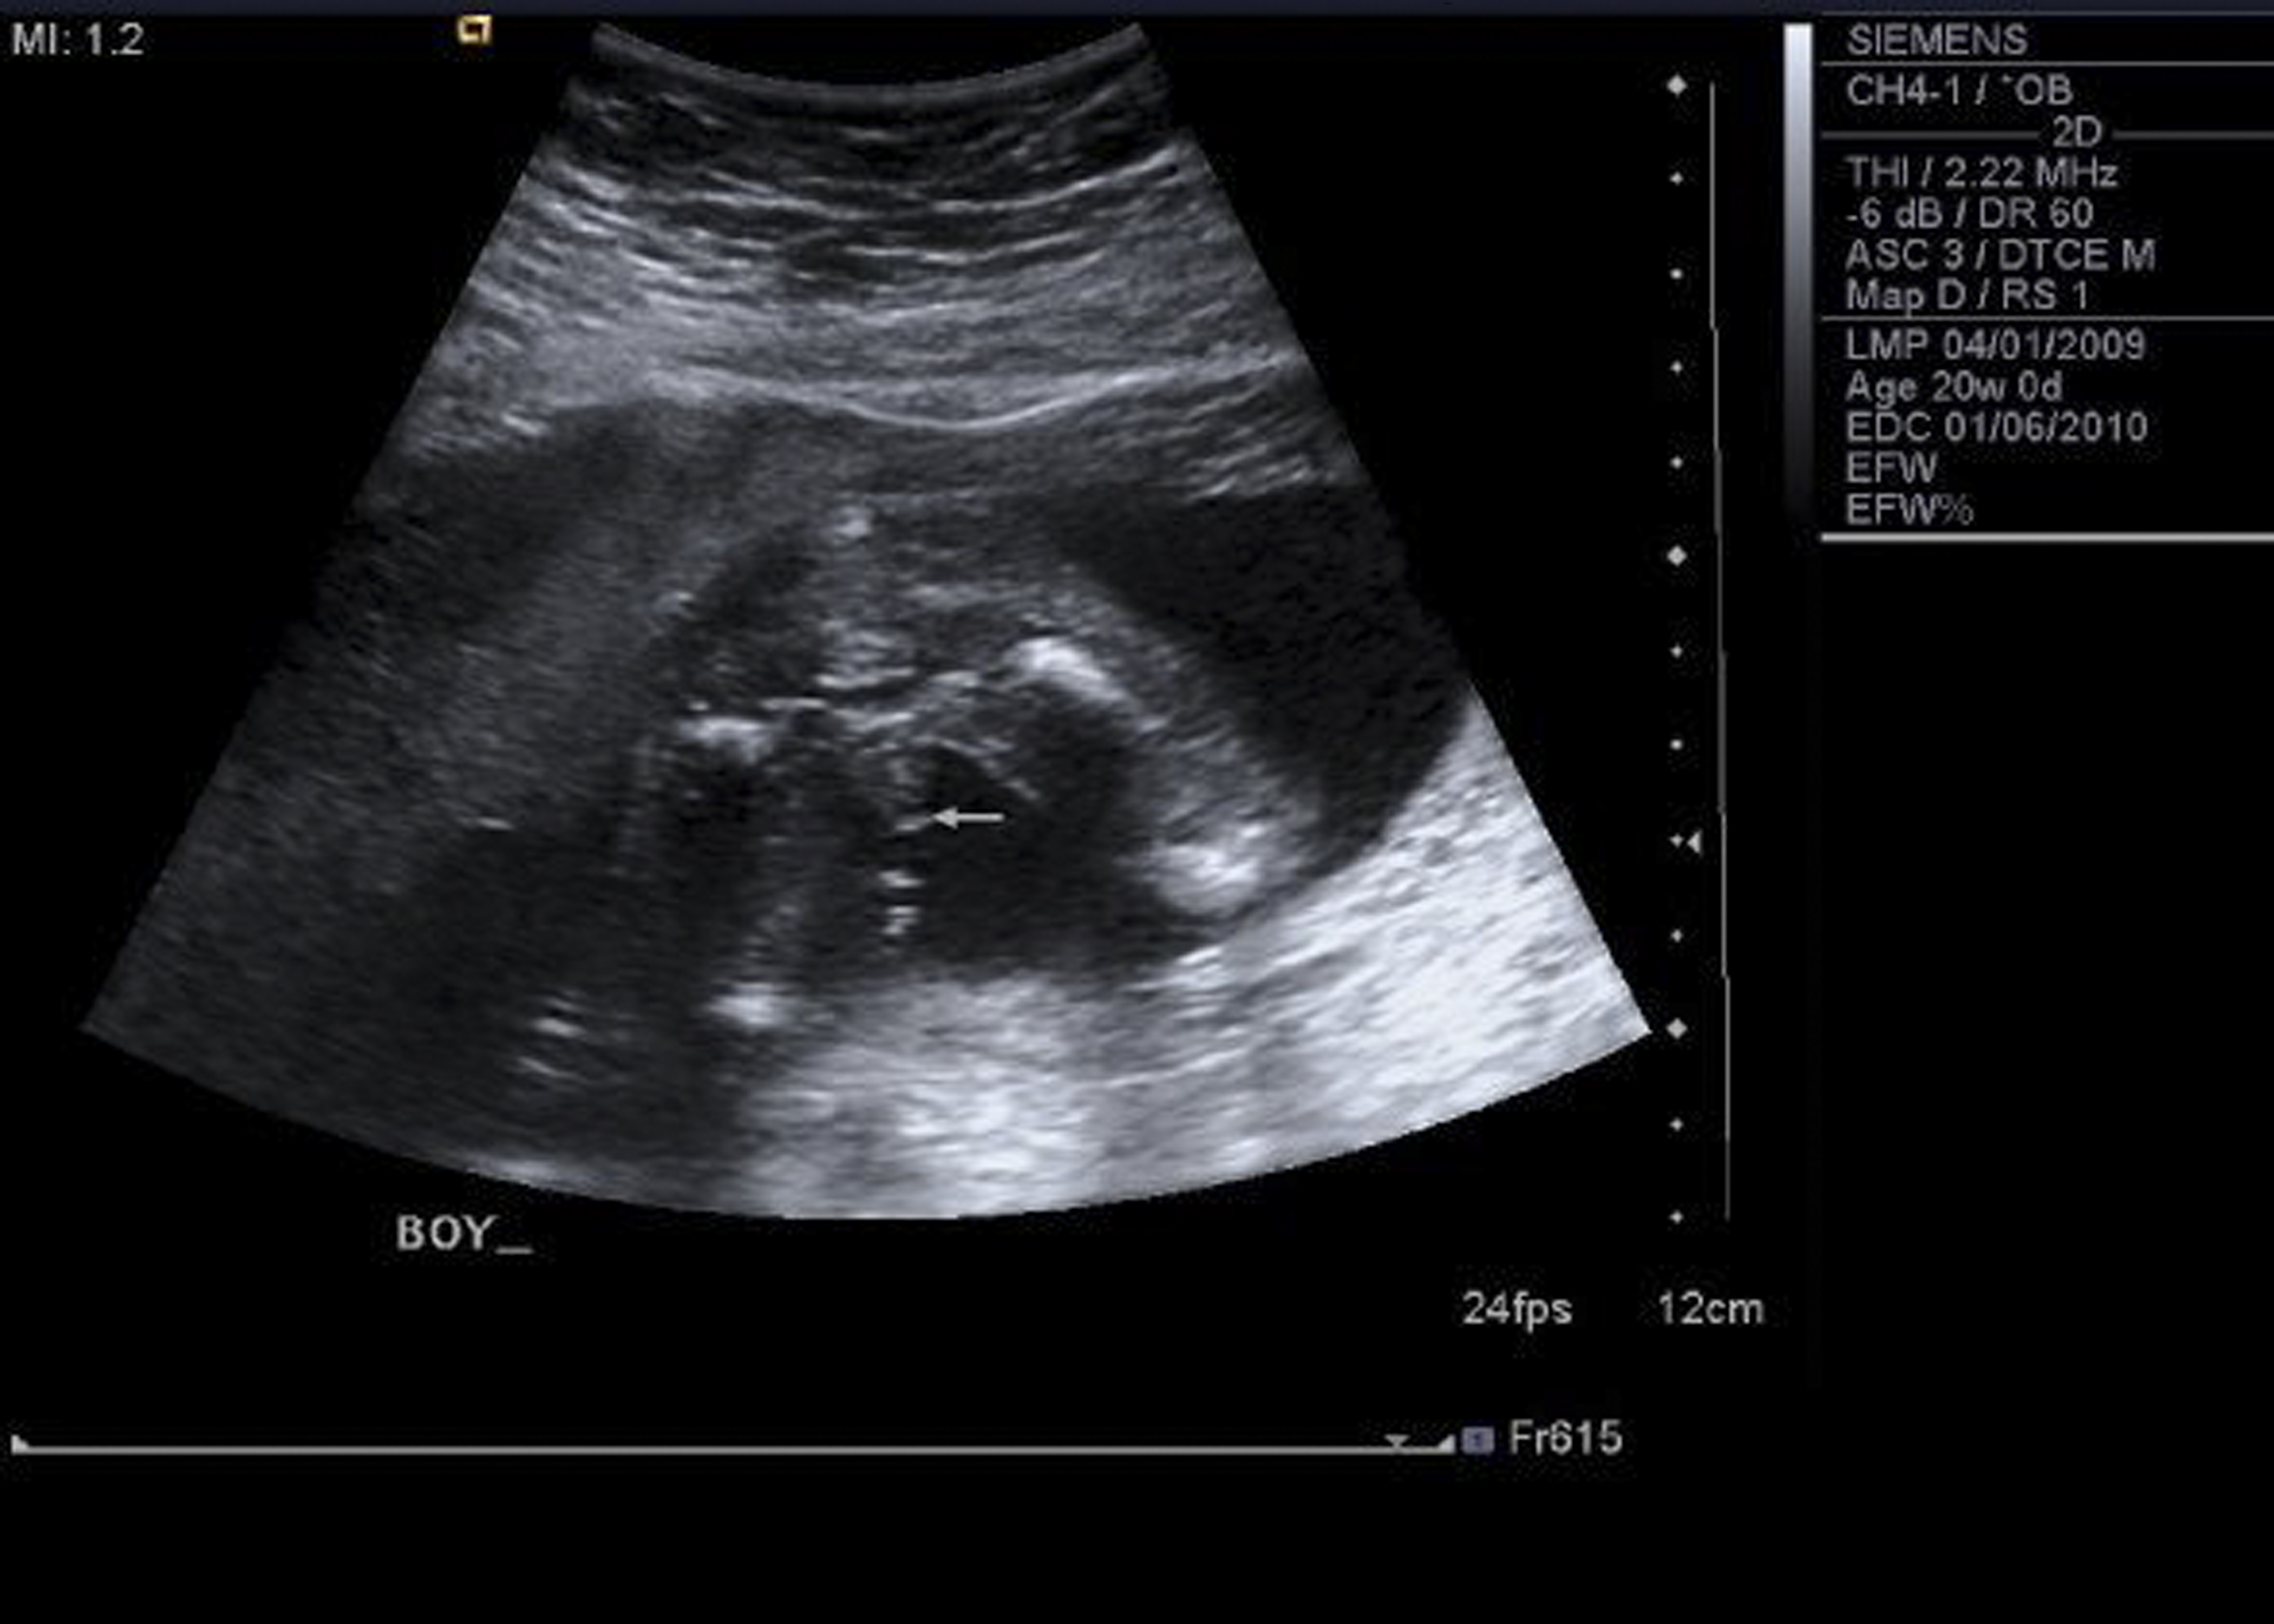

• looks NOTHING like my first son, which is this one.. so i have a hard time believing boy this time